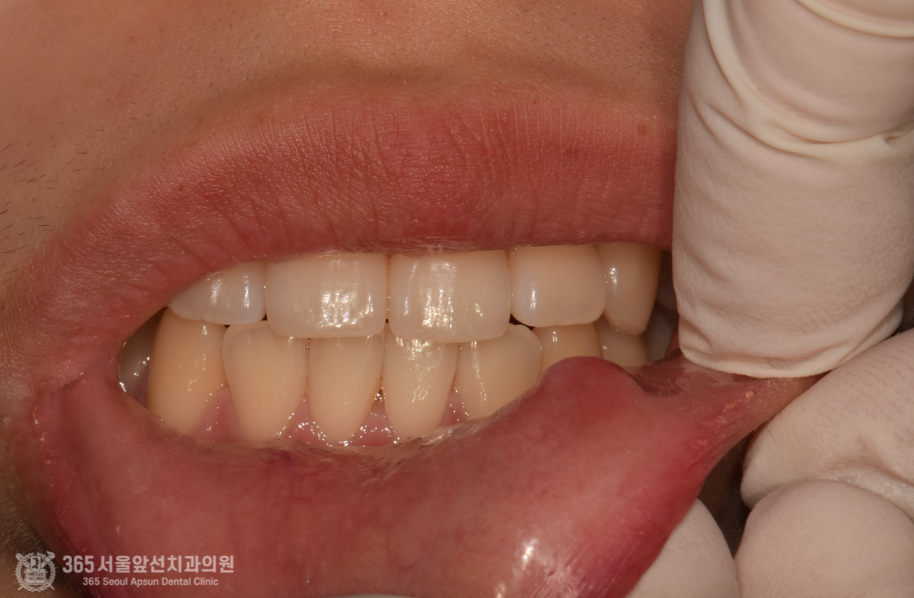

오늘 소개해드릴 증례 환자분은 입술에 점액낭종(mucocele)이 생겨서 불편감을 호소하여 내원하셨던 환자분입니다. 점액낭종이란 어떤 원인에 의해서 침샘 도관이 막히고, 그로인해 분비물이 고여서 생기는 일종의 물혹이라고 이해하시면 쉽겠습니다. ㅎㅎ 촬영일시 : 2024.06.10. 촬영일시 : 2024.06.10. 아랫 입술에 볼록하게 솟은 점액낭종이 관찰됩니다. 터트릴 경우 높은 확률로 재발될 수 있기에 원인이 되는 타액선(침샘)을 포함하여 절제 해내는 것이 치료의 원칙이 되겠습니다. 촬영일시 : 2024.06.10. 조심스럽게 접근하여 원인이 되는 소타액선을 제거합니다. 촬영일시 : 2024.06.17. 대략 1주일 후 회복상태이며 아직까지는 약간의 붓기와 멍이 잔존한 것이 관찰됩니다. 촬영일시 : 2024.06.23. 대략 2주후 모습이며 깨끗하게 제거된 것이 관찰됩니다. 오늘은 입술부위에 종종 생기는 점액낭종(mucocele)에 대해서 알아보았습니다. 점액낭종 자체는 간단하게 제거가 가능하므로 너무 걱정하실 필요는 없겠습니다 ㅎㅎ 그럼 더 좋은 증례와 지식공유로 다시 찾아뵙겠습니다. 이상 미추홀구치과 365서울앞선치과였습니다! [ 치료기간: 2024년 6월10일 ~ 2024년 6월 23일 ] ※ 365서울앞선치과의원의 모든 포스팅은 각 진료과 의료진이 직접 작성합니다. 365서울앞선치과의원 블로그의 임상 케이스 게시물은 환자분께 의학적으로 정확하고 상세한 정보를 드리기 위해 각 진료과 의료진이 직접 작성하며, 모든 증례 사진은 본원 의료진이 직접 시술한 증례를 촬영한 것으로, 의료법 제23조, 제56조에 의거하며 환자분의 동의를 얻어 포스팅에 사용하였습니다. 또한 해당 케이스는 본 환자분의 치료 결과이며, 환자 상태에 따라 치료의 결과는 달라질 수 있습니다. |